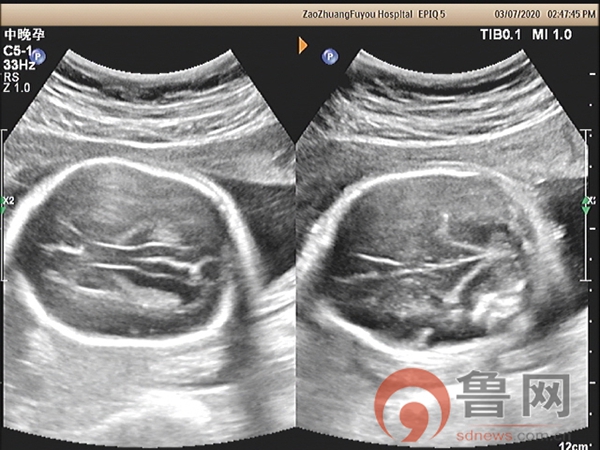

鲁网5月27日讯孕妇张女士(化名),32岁,26孕周+,在外院因胎儿“小脑显示异常”转枣庄市妇幼保健院超声科会诊。接诊医师超声检查发现,胎儿头颅呈“柠檬头”状,小脑呈“香蕉状”并后颅窝池消失,脊柱排列尚规则。随后科室组织专家会诊,经仔细扫查后做出了胎儿“开放性脊柱裂”的诊断,后孕妇转入省级医院进一步检查,与枣庄市妇幼保健院诊断结果一致。之后孕妇在枣庄市妇幼保健院住院引产,证实为“开放性脊柱裂”。

图1:柠檬头,香蕉小脑并后颅窝消失

该孕妇在18孕周唐筛提示神经管缺陷高风险,又进行了无创DNA检查未见染色体异常,18孕周时外院超声检查未发现明显异常,26孕周+时外院因胎儿“小脑显示异常”转枣庄市妇幼保健院超声科会诊。超声检查显示胎儿头颅呈“柠檬头”状,小脑呈“香蕉状”并后颅窝池消失,枣庄市妇幼保健院具有丰富产前超声筛查经验的超声科专家马上意识到,此例胎儿的头部与小脑形态异常,是“开放性脊柱裂”胎儿头部异常的伴发征象。遵循这个思路,随后仔细扫查胎儿脊椎骨,发现脊髓圆锥位置低于腰4以下,骶尾部皮肤回声中断,胎儿脊柱椎体排列尚规则,脊柱无侧弯,无后凸,做出了“开放性脊柱裂”的最终诊断。该例胎儿脊柱的超声异常征象表现细微,远远不如间接征象表现明显,对于经验不足的年轻超声医师极其容易漏诊,因此对本病例诊断过程提出以下思考:

3、除脊柱裂的直接征象外,间接征象对于寻找脊柱裂的证据具有极其重要的作用,如“香蕉小脑”、“柠檬头”、“脊髓圆锥低位”等。